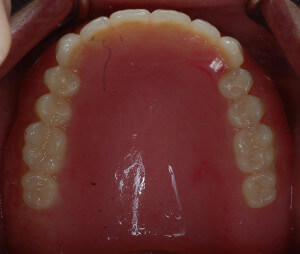

全口活動假牙製作

DSC_3317 DSC_3315

假牙在口內配戴狀況